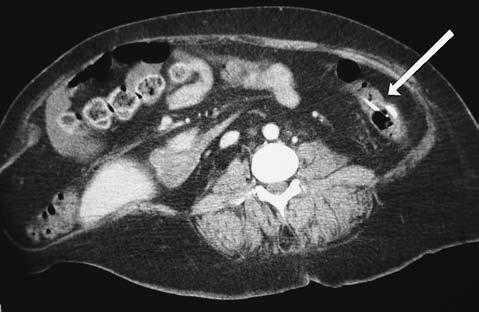

Presentamos el caso de una paciente de 39 años, portadora de una válvula de derivación ventriculoperitoneal por una hidrocefalia normotensiva, que presentó un cuadro de dolor abdominal progresivo, de 24 horas de evolución. La paciente refería cefalea y, en la exploración, presentaba dolor en el hipocondrio y el flanco izquierdo. La analítica evidenció leucocitosis con desviación izquierda. Una tomografía computarizada mostró el catéter situado en la luz del colon, así como peritonitis local con infiltración de la grasa pericolónica (figs. 1 y 2). Se instauró tratamiento antibiótico de amplio espectro y se decidió retirar el catéter de derivación ventriculoperitoneal, y colocar un drenaje externo. La paciente evolucionó satisfactoriamente, y se reimplantó una nueva válvula y un catéter de derivación ventriculoperitoneal.

Fig.2.Corte de tomografía computarizada en el que se observa el catéter dentro de la luz del colon.